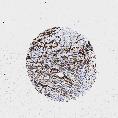

UROTHELIAL CANCER - Protein expressioni

A mouse-over function shows sample information and annotation data. Click on an image to view it in a full screen mode. Samples can be filtered based on level of antibody staining by selecting one or several of the following categories: high, medium, low and not detected. The assay and annotation is described here.

Antibody stainingi

Antibody staining in the annotated cell types in the current human tissue is reported as not detected, low, medium, or high, based on conventional immunohistochemistry profiling in selected tissues. This score is based on the combination of the staining intensity and fraction of stained cells.

Each image is clickable and will lead to virtual microscopy that enables deeper exploration of all samples and also displays staining intensity scores, fraction scores and subcellular localization as well as patient and tissue information for each sample.

Antibody HPA002465

Antibody CAB000031

Staining

High

Medium

Low

Not detected

Intensity

Strong

Moderate

Weak

Negative

Quantity

>75%

75%-25%

<25%

None

Location

Nuclear

Cytoplasmic/membranous

Cytoplasmic/membranous,nuclear

Urothelial carcinoma, High grade

Urothelial carcinoma, Low grade

Adenocarcinoma, NOS